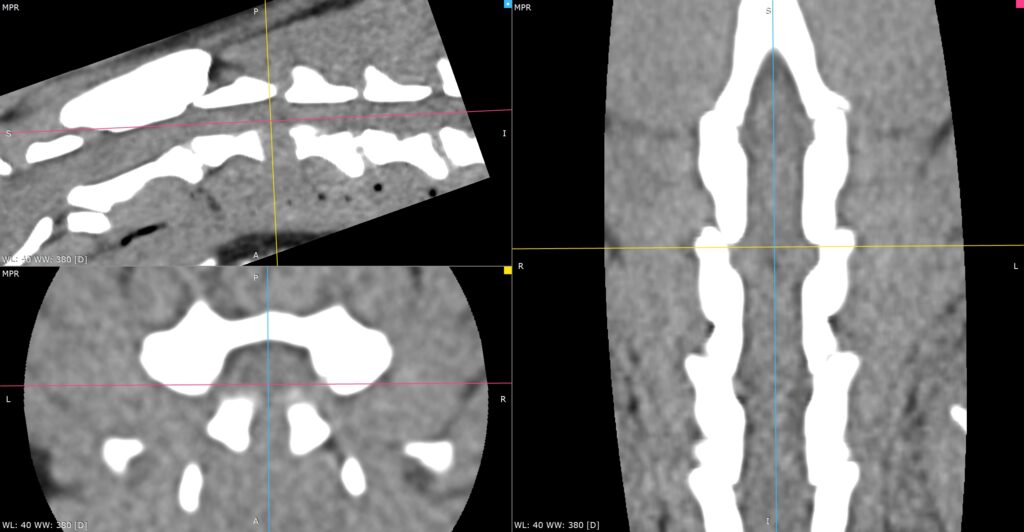

Discospondylite L6-L7 sur un Setter gordon.

• En neurologie et neurochirurgie, le scanner est très performant pour l’exploration des affections d’origine osseuse ou discale. Il permet de détecter les hernies discales calcifiées, les malformations vertébrales, les fractures vertébrales, les instabilités, ainsi que certaines compressions médullaires d’origine osseuse. Il est également utile pour l’exploration de certaines affections intracrâniennes, notamment lorsqu’elles impliquent des structures osseuses.